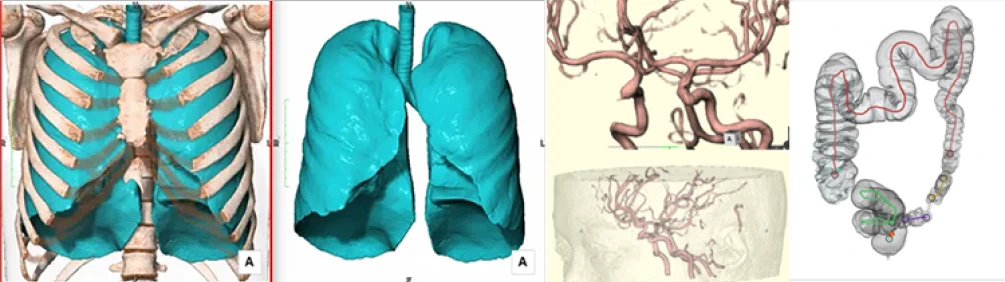

AI を搭載した最新鋭MRI・CTを導入

医療技術の進化を取り入れ、高精度な検査を実現。AI による画像解析により、見落としのリスクを最小限に抑えます。

高原クリニック イノベーティブスキャンのMRIは、すい臓がんの早期発見において高精度な診断を実現しています。